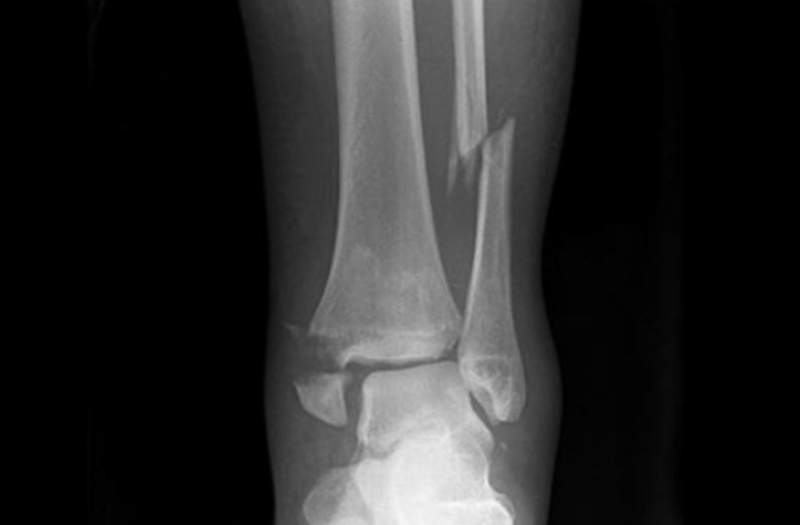

不过一位马来西亚男子成功练了2个月,体重从78公斤降至65公斤,有没有锻炼出肌肉不晓得,唯一知道的是因为这训练法太魔鬼了导致踝关节骨折需要休息八周….

同事在两个月内完成一拳超人训练,从78公斤减到65公斤,不幸的是他踝关节骨折需要休息八周。这种训练要密集锻链,得每天这样做,我想说你得了解自己的身体状况而不是直接照做。